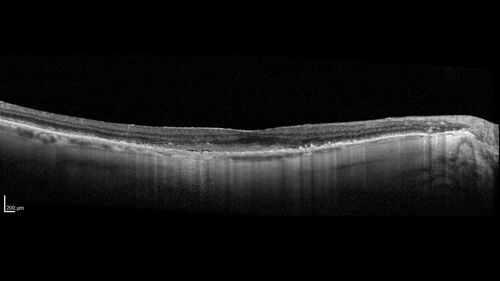

wet AMD with classic extrafoveal macular neovascularization in the good eye

89 year old man with longstanding vision loss in the left eye presented with one month of mild vision loss in the right eye.  Vision was 20/32.  This eye responded to vabysmo therapy.